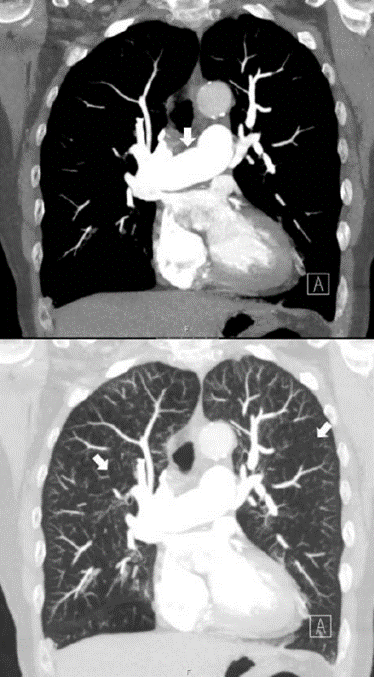

Vad ser du på bilden?

DT thorax utförd med intravenös kontrast på lungembolifrågeställning. Två koronara snitt i höjd med truncus pulmonalis; den övre bilden i mediastinumfönster och den nedre i lungfönster.

Notera hur breddökad truncus pulmonalis (indikerad med pil på den övre bilden) är i förhållande till arcus aortae, vilket är ett tydligt tecken på högt tryck i lungkretsloppet. Notera också generellt fläckvis varierande attenuering (kärlen syns inte, svart bild liksom, kan innebära luft som fastnar i experium) i lungparenkymet (indikerat med pilar i nedre bilden), ett mönster som kallas mosaik pattern. Ett litet infiltrat ses lateralt-basalt i höger lunga.

Vad säger oss fyndet av ”mosaik pattern i inspiration” och ”air-trapping” på DT?

CTEPH kan ge denna bilden med pulmonell hypertension